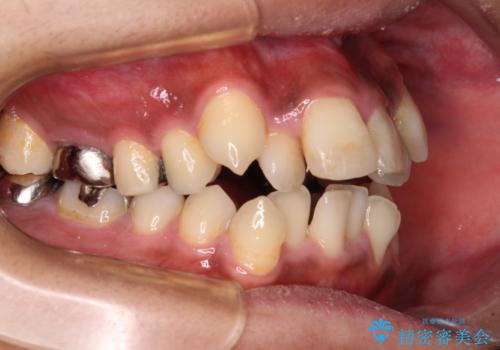

八重歯と開咬 ワイヤー装置での抜歯矯正

- 前歯のデコボコと八重歯、開咬を気にして来院された患者様です。

骨格的に下顎骨が上顎骨に対して後退位であったため、上顎の左右第一小臼歯を抜歯し、デコボコを改善するとともに開咬を改善していくこととしました。